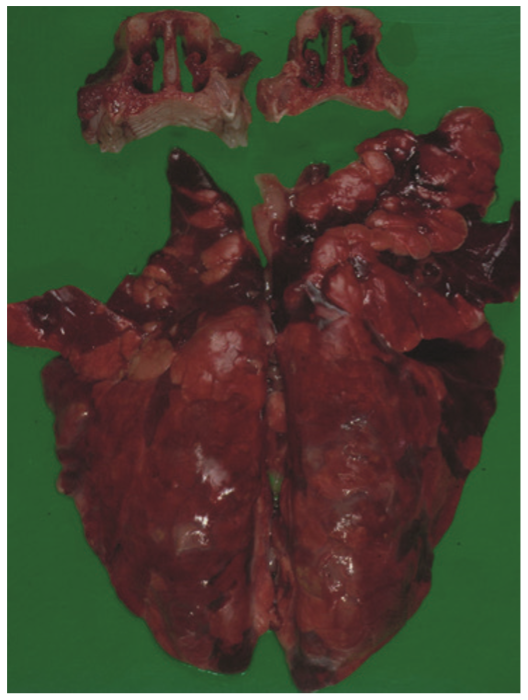

Figure 2.

Turbinate and lung lesions in a nursery pig affected by Bordetella bronchiseptica.© Histology and Anatomical Pathology, Faculty of Veterinary Medicine, University of Murcia.

Pulmonary infection with Bordetella bronchiseptica results in suppurative bronchopneumonia (Figure 2). It can act as the primary etiologic agent in young pigs and in older pigs it generally contributes to the severity of the Porcine Respiratory Disease Complex (PRDC) through interaction with other bacteria and viruses in mixed infections. The necrosis and tissue damage associated with Bordetella bronchiseptica pneumonia is induced by the action of DNT, without which pneumonia does not develop. The most prevalent clinical sign of Bordetella bronchiseptica pneumonia is coughing and it can be difficult to discern the cause without further diagnostics.